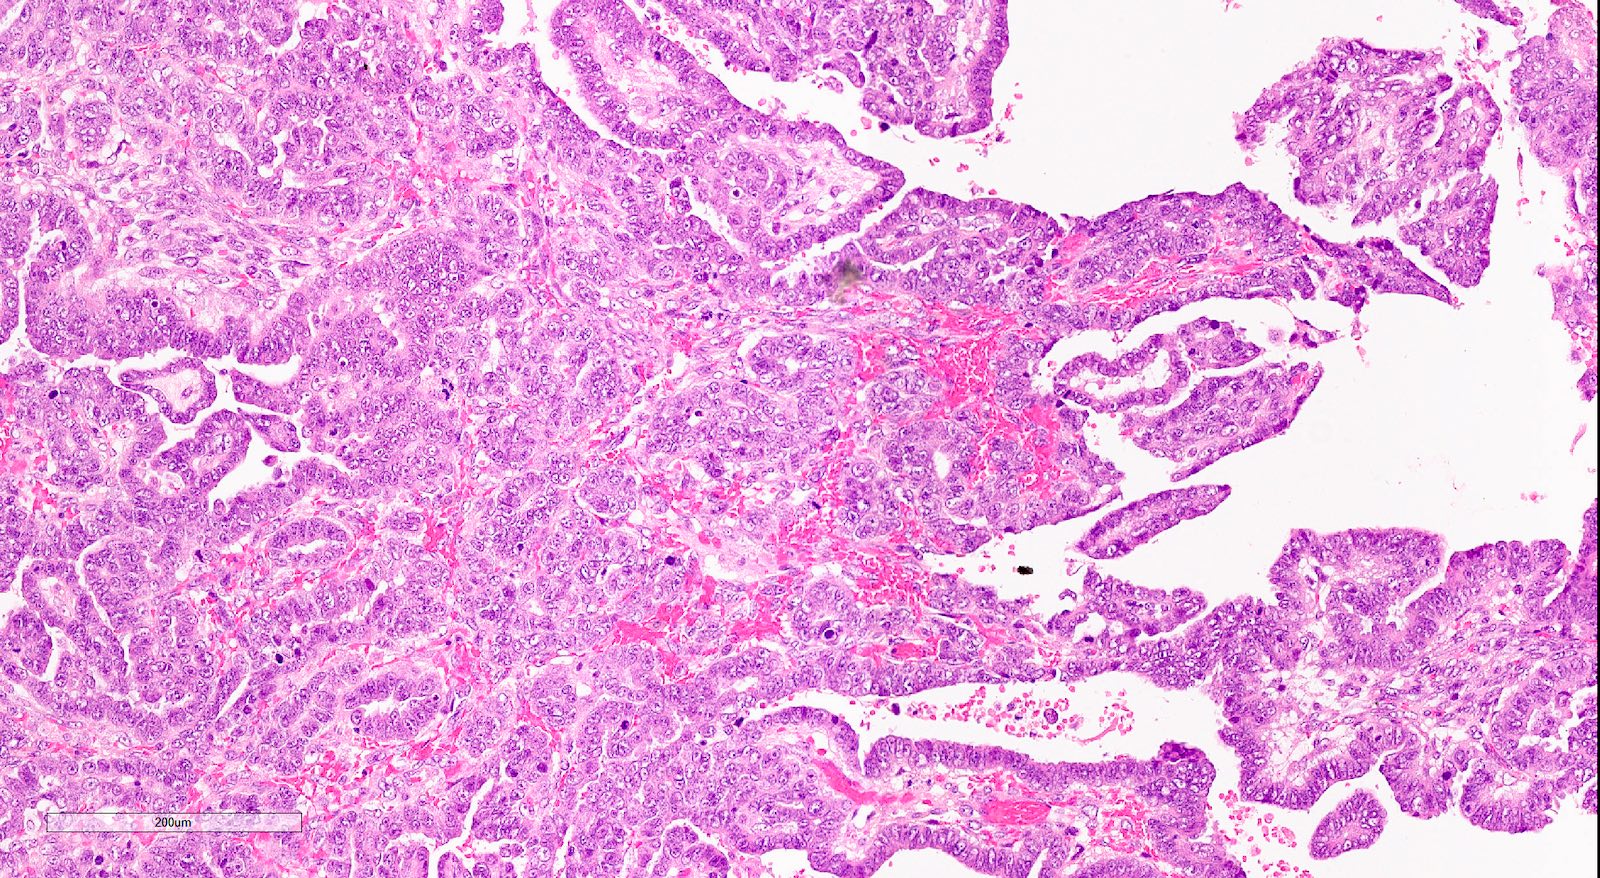

Microscopic (histologic) description

- Biphasic tumor with carcinomatous and sarcomatous elements, both high grade (Int J Gynecol Pathol 1990;9:1)

- Carcinomatous and sarcomatous components are juxtaposed

- Carcinomatous elements:

- Often high grade endometrioid or serous carcinoma, frequently admixed

- More uncommonly clear cell carcinoma

- 50 - 75% of cases have serous or mixed serous and high grade endometrioid carcinoma (Am J Surg Pathol 2007;31:1653)

- Hybrid morphology between endometrioid and serous carcinoma is frequent, as is undifferentiated carcinoma (Mod Pathol 2010;23:781)

- Other components that can be rarely found are squamous, mucinous and neuroendocrine

- Angiolymphatic invasion common, more commonly of the carcinomatous component

Microscopic (histologic) images